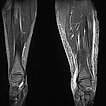

Koronare, T2-gewichtete, fettunterdrückte MRT der Unterschenkel beidseits. Auf der betroffenen linken Seite ausgeprägtes subkutanes Ödem durch den chronischen Venenhochdruck.